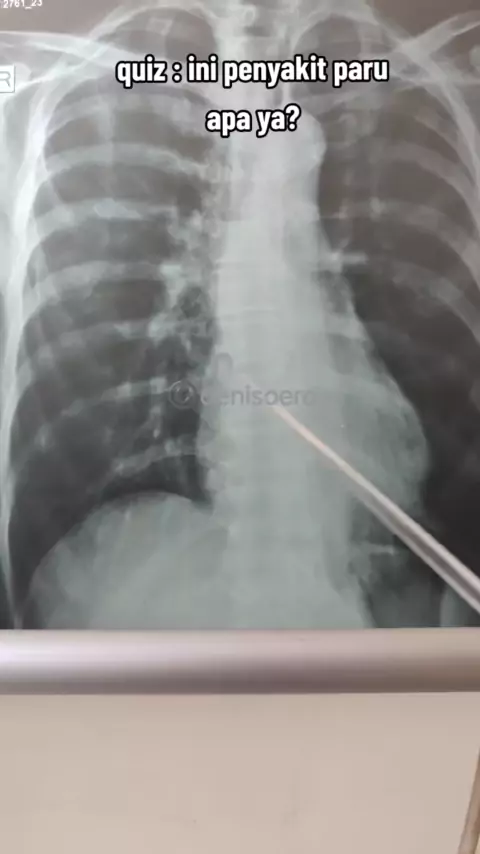

quiz : ini penyakit paru apa ya? obatnya apa ya? pasien keluhan sesak napas(+),batuk(-),cepat capek,ngos"an,tulis di kolom.komentar, terima kasih#quiz#quiz#rontgen2023#parufans#paruparu#radiologi#chestxray#thorax#toraks#dokterparu#dokterviral#spesialisparumedan#spesialisparu#゚#p